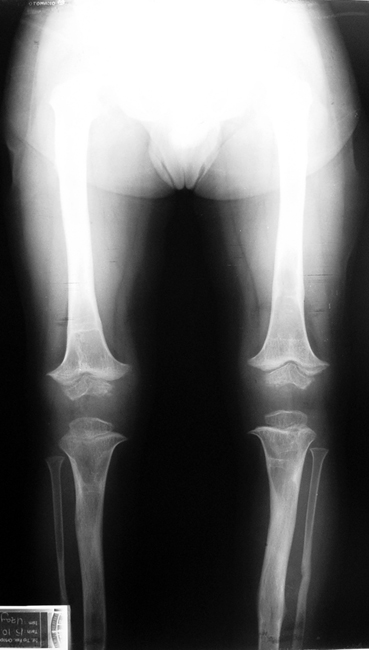

Cücelerde boy kısalığı için uyguladığımız boy uzatma programında sadece boy uzatmayı değil aynı zamanda ayak bileği, diz , kalça ve el bileği deformitelerinin düzeltilmesini ve lomber hiperlordozun azaltılmasını amaçlamaktayız. Lomber hiperlordozun azaltılması yetişkin yaşlarda spinal stenoz riskini azaltır. Başvuru anındaki yaşına göre iki tip tedavi stratejisi bulunmaktadır.

6-8 yaşları arasında Femur (uyluk) ve tibiada (bacak) toplam 10cm boy uzatma (6cm femur ve 4 cm tibia) Parantez bacak deformitesinin düzeltilmesi Ortalama eksternal fiksasyon tedavi süresi = 5 ay İkinci, üçüncü ve dördüncü boy uzatmalar Yetişkin stratejisinde (aşağıda) olduğu gibi Alt uzuvlarda (Diz üstü ve altı dahil) toplam 30-35 cm boy uzatma Üst uzuvlarda toplam 10-12 cm boy uzatma

12-14 yaşları arasında Her iki tibiada toplam 10-15cm boy uzatma (iki seviyeli uzatma) Proksimal tibianın varus deformitesini proksimal osteotomi ile düzeltilmesi Distal tibianın varus deformitesi distal osteotomi ile düzeltmesi Distal tibianın varus deformitesi distal osteotomi ile düzeltmesi Boy uzatmanın sonunda lateral kollateral ligamentin gerilmesi Ortalama eksternal fiksasyon tedavi süresi = 8-10 ay